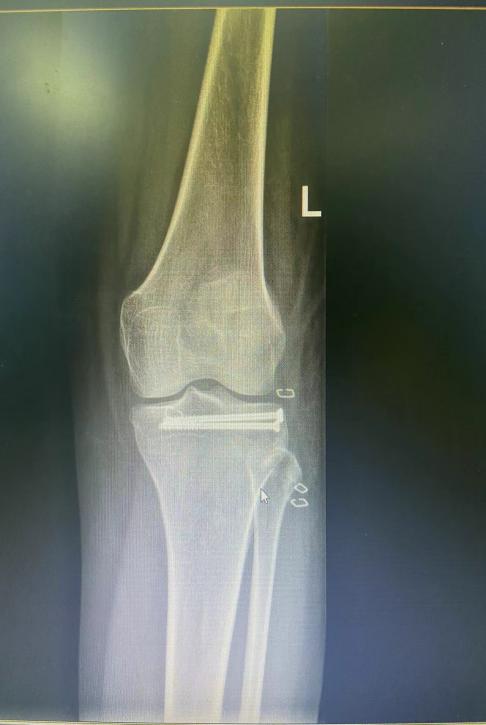

微创切口

术后X片

据严伟主任介绍,胫骨平台单纯后外侧塌陷骨折处理较为棘手,传统开放复位内固定治疗方式手术创伤大,影响膝关节功能。随着关节镜技术发展,应用关节镜辅助复位治疗单纯后外侧平台塌陷型骨折临床效果满意,创伤小并有利于患者康复,值得推广应用。(供稿:谢迎)